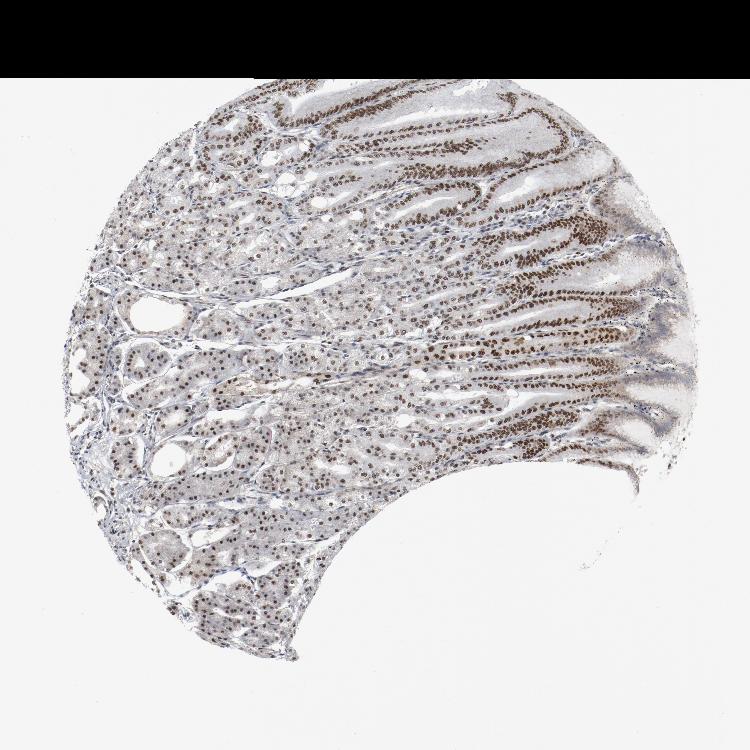

TISSUE PRIMARY DATA STOMACH Show tissue menu

STOMACH 1 - Antibody stainingi

Antibody staining in the annotated cell types in the current human tissue is reported as not detected, low, medium, or high, based on conventional immunohistochemistry profiling in selected tissues. This score is based on the combination of the staining intensity and fraction of stained cells.

Each image is clickable and will lead to virtual microscopy that enables deeper exploration of all samples and also displays staining intensity scores, fraction scores and subcellular localization as well as patient and tissue information for each sample.

Antibody HPA074031Antibody CAB004548

Glandular cells HighHigh

STOMACH 2 - Antibody stainingi

Glandular cells HighMedium